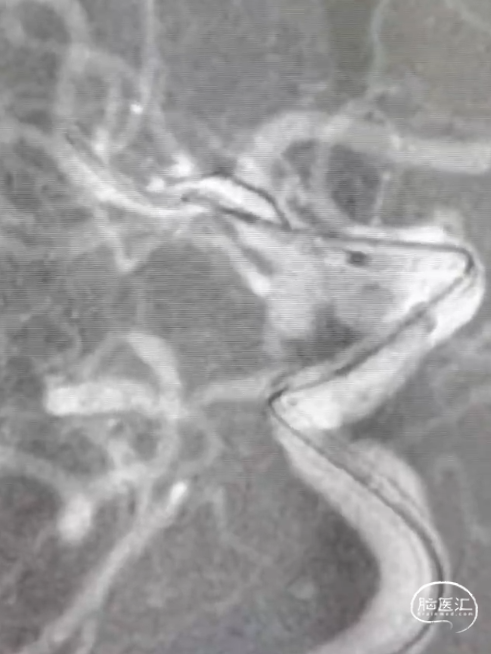

· 头颈部CTA示:脑动脉硬化,双侧颈总动脉分叉处、双侧颈内动脉虹吸段钙化斑块形成;考虑右侧颈内动脉C7段动脉瘤;右侧胚胎型大脑后动脉;左侧大脑动脉P1段、P2段局部轻度狭窄。

3D造影测量右侧颈内动脉C7段动脉瘤,动脉瘤瘤颈宽。